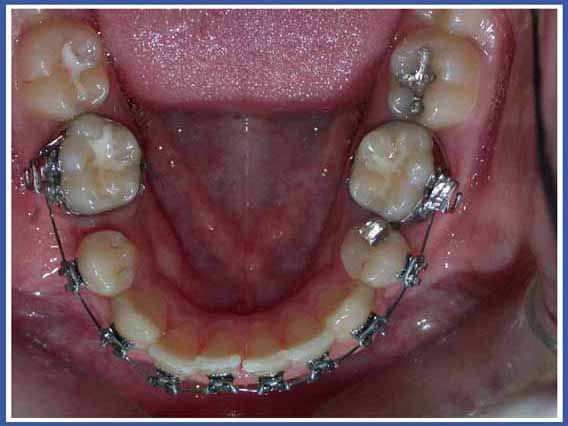

Удерживатель пространства – это маленькое металлическое приспособление, которое подготавливается и приспосабливается индивидуально для вашего ребенка в соответствии со строением его рта. Оно надежно закрепляется во рту и будет снято только тогда, когда постоянный зуб займет правильное для себя место. Это приспособление обычно строится из металлического колечка, приклеиваемого к соседнему зубу, и металлической трубочки, присоединенной к нему и опирающейся на соседние зубы. Целью использования приспособления является стабилизация зубов, оставшихся по сторонам промежутка, а также предотвращение их смещения в сторону этого промежутка до того момента, когда прорезавшийся постоянный зуб займет свое место.